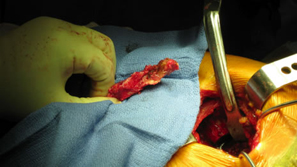

| Removal of Hardware (two screws) |

The Midas Rex® power system was used to cut the distal portion of the stem off.

| The stem fit was excellent with impressive implant to bone stability. The proximal modular neck design allowed selection of a variety of femoral offsets and neck lengths. This along with large head M-O-M (40mm) bearings provided significant ROM and hip joint stability. The short stem functions as a pilot with implant to bone stability provided by proximal stem geometry (cone & triangle). |